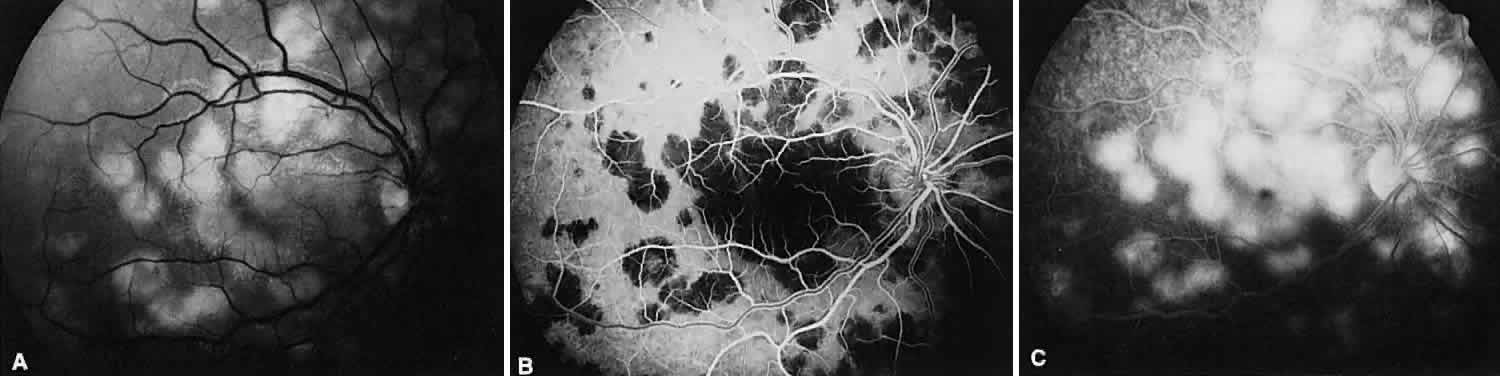

BIRDSHOT RETINOCHOROIDOPATHY

Birdshot retinochoroidopathy (also known as vitiliginous chorioretinitis) presents bilaterally, generally in middle-aged women, causing floaters and decreased vision, night blindness, and color blindness. Clinically, there are patches of postequatorial choroidal and retinal pigment epithelial depigmentation (Fig. 10A), vitreous cells, macular and disc edema, and venous sheathing. SRNV frequently is a late sequela. Often central vision may be preserved in at least one eye.

Fig. 10. Birdshot retinochoroidopathy. A. Multiple cream-color deep choroidal lesions. B. Fluorescein angiogram shows leakage of the optic disc and the retinal vasculature. C. Indocyanine green angiography showing areas of hypofluorescence that exceed those observed on fluorescein angiography.

On fluorescein angiography, retinal vessel staining, disc leakage, and cystoid macular edema are found (see Fig. 10B). There often is generalized hypofluorescence of the retinal vessels and increased circulation time.35,36 Surprisingly, the patches of depigmentation may appear normal on angiography, although there can be mild late hyperfluorescence.35,36 Posterior pole choroidal hyperfluorescent lesions that correspond to the areas of depigmentation and SRNV also can be seen.37

On ICG angiography (see Fig. 10C), early and late hypofluorescent patches, exceeding the clinically detectable lesions, with a choroidal vasotropic distribution and relative sparing of the peripapillary area and the central macula, are noted. These findings differentiate this condition from AMPPPE, multifocal choroiditis, and other granulomatous conditions such as sarcoidosis and sympathetic ophthalmia. Rarely, hyperfluorescent spots are noted in the late phases of the angiogram, which correspond ophthalmoscopically to retinal inflammation or obstructive changes.38